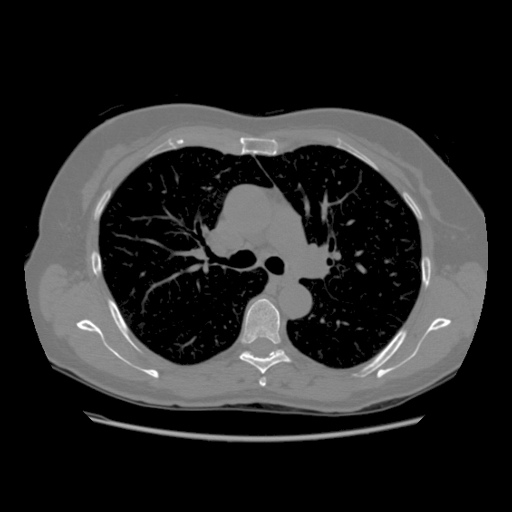

IV-C Few-View CT Reconstruction

In this section, the reconstruction performance of our proposed framework under few-view conditions will be tested. For the parallel and fan beam geometry, the number of views increases from to , uniformly distributing from to and to respectively. Such settings provide a complete benchmark of reconstruction performance, ranging from extremely sparse to relatively complete, full-view CT reconstruction. The experiment results are shown in Fig.5. Additionally, the ground truth, few-view ( views), and full-view ( views) CT reconstruction results of different methods are shown in the first and third rows of Fig.7 (parallel-beam, LIDC-IDRI dataset), and Fig.8 (fan-beam, LIDC-IDRI dataset).

IV-D Limited-Angle CT Reconstruction

To test the proposed framework’s performance on limited-angle reconstruction, we redo the experiment in the above section with the angular range changing from to for parallel-beam geometry and to for fan-beam geometry, one projection per degree. The experiment results are shown in Fig.6. Also, the ground truth and the limited-angle CT reconstruction results of different methods are shown in the row of Fig.7 (parallel-beam, LIDC-IDRI dataset), and Fig.8 (fan-beam, LIDC-IDRI dataset).